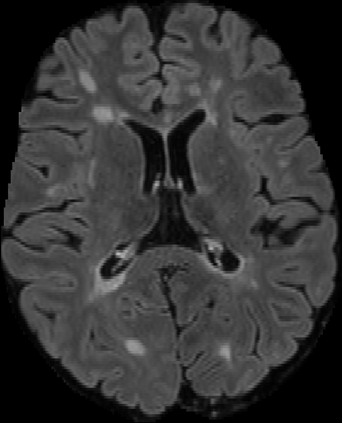

Assessment of lesions and their longitudinal progression from brain magnetic resonance (MR) images plays a crucial role in diagnosing and monitoring multiple sclerosis (MS). Machine learning models have demonstrated a great potential for automated MS lesion segmentation. Training such models typically requires large-scale high-quality datasets that are consistently annotated. However, MS imaging datasets are often small, segregated across multiple sites, with different formats (cross-sectional or longitudinal), and diverse annotation styles. This poses a significant challenge to train a unified MS lesion segmentation model. To tackle this challenge, we present SegHeD, a novel multi-dataset multi-task segmentation model that can incorporate heterogeneous data as input and perform all-lesion, new-lesion, as well as vanishing-lesion segmentation. Furthermore, we account for domain knowledge about MS lesions, incorporating longitudinal, spatial, and volumetric constraints into the segmentation model. SegHeD is assessed on five MS datasets and achieves a high performance in all, new, and vanishing-lesion segmentation, outperforming several state-of-the-art methods in this field.